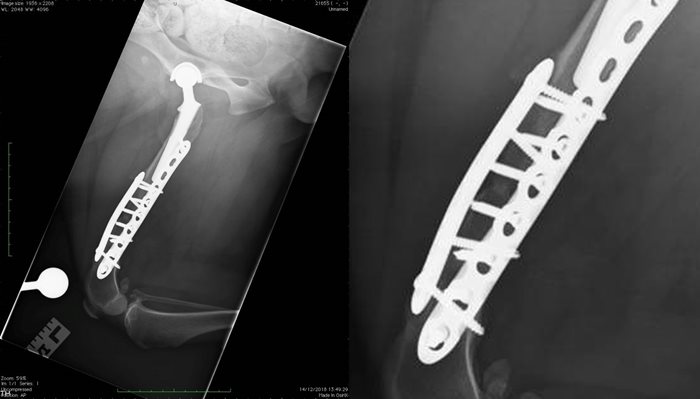

The client was presented to SCVS for four sessions of ESWT which were well-tolerated. The client was then presented to SCVS for further re-examination after these ESWT sessions when palpation of the femoral osteotomy site was well-tolerated. Femoral radiography performed at this time (as seen below) demonstrated clinical union of the osteotomy. The owner and clinician also reported an overall improvement with regards to the clients levels of comfort, and improved lameness.